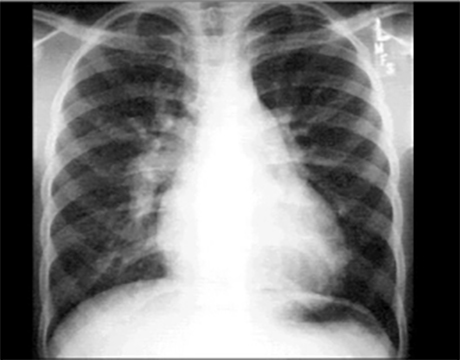

PA and Lateral

Click on the Xrays to enlarge them.

Choose the best interpretation of the chest X rays:

Dilated pulmonary trunk

RV enlargement + dilated

pulmonary trunk +

increased pulmonary vascularity

RV enlargement +

LA enlargement

RV enlargement + small pulmonary trunk +

decreased pulmonary vascularity

Normal